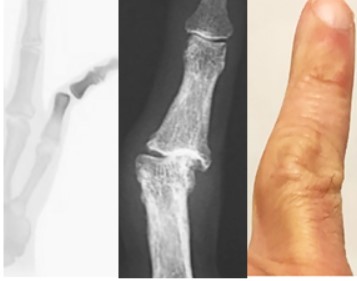

Las lesiones de la mano del arquero se producirán generalmente en la fase de acción. En esta se pueden producir tres acciones técnicas diferentes: el bloqueo, el desvío y el despeje [4]. (1) Bloqueo: el arquero espera la pelota con una flexión del codo de unos 140° y una extensión de la muñeca de unos 40°. A nivel metacarpofalángico e interfalángico existe un equilibrio entre flexores y extensores y el pulgar en discreta abducción. Cuando llega la pelota, hay una resistencia de los extensores de los dedos y de la muñeca; posteriormente hay un movimiento de flexión, con el balón en las manos, gracias a una discreta aducción y flexión de la muñeca acompañada de una potente flexión de los dedos. Luego hay una protección instintiva del balón por las manos y cuerpo. Aquí por amenaza de un contrario se puede producir contusiones sobre las manos, principalmente a nivel de los metacarpianos. (2) Desvío: En esta acción el miembro superior está en extensión completa y contraído para resistir la fuerza del balón, y así desviarlo. Esta situación puede provocar lesiones a nivel de las articulaciones interfalángicas. Ejemplo típico es el enganche del dedo meñique en el suelo, lesionando cápsula y ligamento lateral interno de articulación interfalángica proximal (Figura 2).  (3) Despeje: Es un “puñetazo” a la pelota, que nos recuerda a la mano del boxeador. Puede producir lesiones en el carpo. Ejemplo es despejar con los puños en un tiro de esquina.

Figura 2. Luxación IFP, artrosis meñique y deformidad característica del arquero

A su vez, podemos clasificar estas lesiones en agudas y crónicas. En las lesiones agudas tendremos lesiones: capsulares, ligamentosas, tendinosas y óseas [5].

Lesiones agudas

• Lesiones capsulares

Por caída de una pelota sobre el dedo en extensión, produciendo un mecanismo de hiperextensión a nivel de la articulación interfalángica proximal, con lesión de la placa volar. Se producen en el desvío o en un bloqueo. El tratamiento seria tres o cuatro semanas de inmovilización con la interfalángica proximal a 15° - 30° de flexión. Pero en arqueros profesionales se tratarán con vendajes funcionales, con secuelas mínimas a corto plazo que darán lesiones degenerativas a largo plazo.

• Lesiones ligamentosas:

Son las más frecuentes y generalmente parciales. También se producen en el desvío, en el bloqueo (articulación metacarpofalángica del pulgar) y en las caídas. El tratamiento debería ser inmovilizar las articulaciones interfalángicas flexionadas durante tres semanas. El tratamiento en el profesionalismo será con vendajes funcional.

• Lesiones tendinosas:

Las más comunes son las roturas del extensor en dorso de falanges distales. El mecanismo es por flexión violenta de la falange distal cuando la interfalángica distal está en extensión activa. Puede producir un arrancamiento óseo extraarticular y provocando una fractura intraarticular. Clínicamente la falange distal está una flexión con una incapacidad a la extensión dando lugar al dedo en martillo o "mallet-finger". Esta lesión en los niños puede producir una epifisiolisis. El tratamiento ortopédico (falange distal en hiperextensión durante 4 a 6 semanas con la articulación interfalángica proximal libre), o tratamiento quirúrgico.

Las luxaciones interfalángicas son consecuencia de la asociación de estas tres lesiones agudas. Se producen en choques directos. Las luxaciones más frecuentes son las interfalángicas proximales. Estas generalmente se reducen en el campo de juego, no acudiendo a la consulta médica. Solo se opera cuando no se logre una reducción perfecta o cuando existe una gran inestabilidad. El tratamiento de las luxaciones metacarpofalángicas (muy poco frecuentes) generalmente se resuelven en forma quirúrgica.

• Lesiones óseas:

Se producen por caída o choque directo, al despejar un balón o protegiendo la pelota tras el bloqueo. Las fracturas más frecuentes serán las de los metacarpianos (cuarto, quinto metacarpiano), fracturas del tercio distal del radio, escafoides [6] y falanges. Los tratamientos serán ortopédicos o quirúrgicos.

Lesiones crónicas

Las lesiones crónicas estarán relacionadas con los tratamientos incorrectos de las lesiones agudas y con el impacto repetitivo que recibe la articulación radiocarpiana al atrapar el balón. Pensemos que en un entrenamiento el arquero puede contactar el balón unas 100 veces. Alteraciones del escafoides, son muestra evidente de ello. De esta manera tenemos las "manos del portero de fútbol" [7]. Estas tienen una articulación radio-cubital ancha, con un leve déficit en la extensión de la muñeca y con ensanchamiento residual en articulaciones interfalángicas. (Figura 3).

A pesar de ello los arqueros pueden realizar sus trabajos habituales sin problema alguno.                                                                                                              Prácticamente no hay registros de estas lesiones, ya que, al ser bien toleradas, los arqueros no pierden días de actividad y no entran en la definición de lesión deportiva.

Figura 3. Deformidad del meñique tras tratamiento conservador y fractura de escafoides